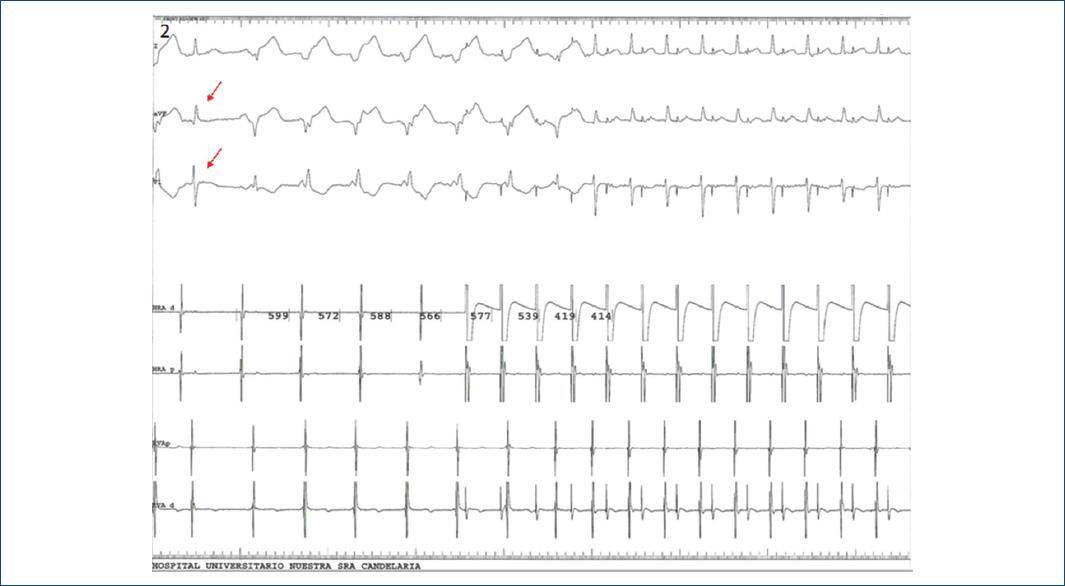

TAQUICARDIA VENTRICULAR PAROXISTICA Ritmo activo caracterizado por la presencia de 3 o mas latidos sucesivos originados por debajo de la bifurcacin del Haz de His. Ritmo ECG se caracteriza por la lenta deformidad y complejo QRS ancho el tiempo QRS menudo excede 016s ritmo cardaco 30-40 lat min marcapasos ectpico distal de rama ms cerca el tiempo QRS es ms largo la deformidad ms evidente de la frecuencia ventricular es ms lenta e. Fue una lstima no haber contado con un registro electrocardiogrfico.

This reference guide requires a paid plan. Este ritmo ventricular disociado del ritmo de las aurculas que es ms lento difiere del ritmo idioventricular habitual ms lento 30 a 40 por minuto y del de las taquicardias ventriculares clsicas ms rpidas 140 a 200 por minuto. El ritmo de escape ventricular se observa en el electrocardiograma como un ritmo regular lento entre 20 y 50 lpm y con QRS anchos.